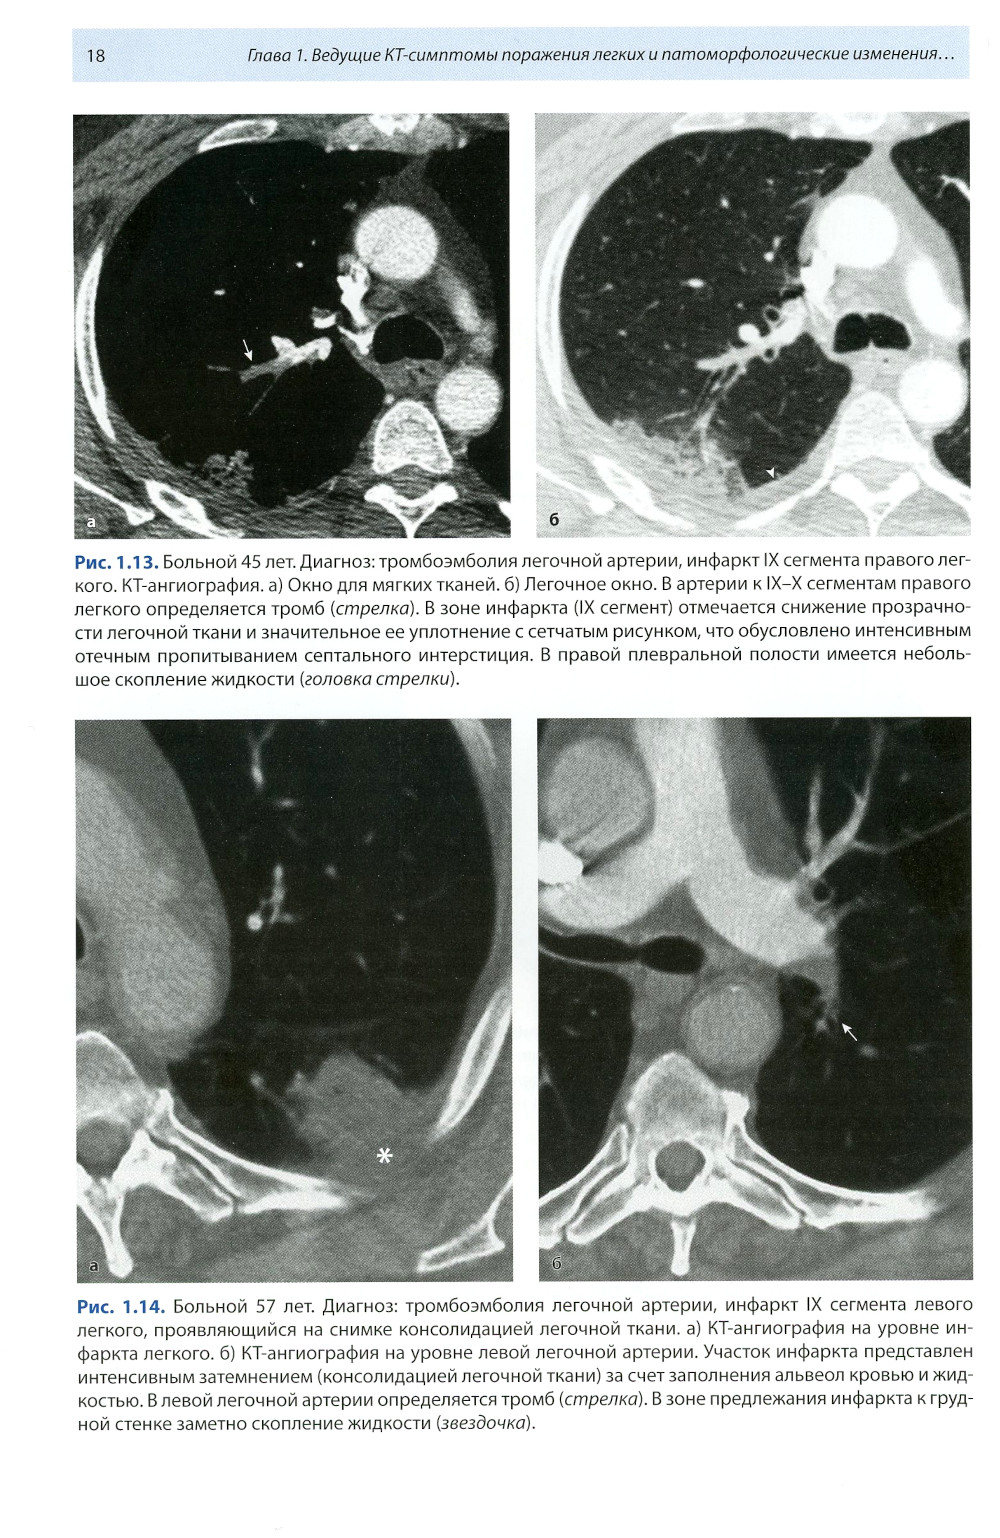

Книга составлена из двух разделов. В первом (глава 1) описаны основные симптомы патологии легких, выявляемые при КТ. Каждый из них представлен с позиции отображающих его морфологических изменений. В краткой форме описаны заболевания, проявляющиеся конкретным симптомом. Второй раздел книги состоит из трех глав, в которых отражены современные взгляды на наиболее часто встречающуюся патологию легких (пневмония, туберкулез, рак) и показаны возможности КТ в выявлении этих заболеваний. Издание предназначено для врачей лучевой диагностики, терапевтов, интернов и студентов старших курсов, интересующихся проблемами рентгенологии.| Издательство | МЕДпресс-информ |